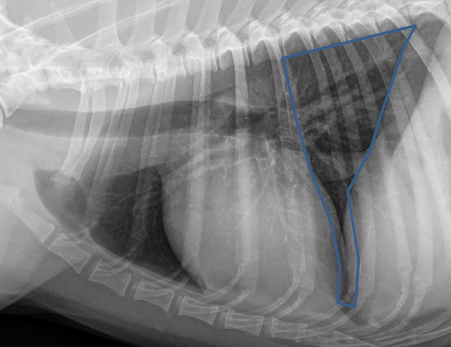

Lateral

12 to 2

Left atrium

Aortic arch

Arteries up and away

Veins ventral and central

Ascending aorta

Right auricle

Pulmonary artery

Right ventricle

Red Cupula

Blue Crura